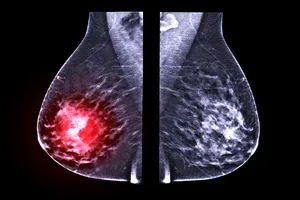

유방암의 병기는 암의 진행 정도를 나타내는 지표로, 종양의 크기(T), 림프절 전이(N), 원격 전이(M) 등을 종합적으로 고려하여 분류합니다. 병기별 특징과 예후는 다음과 같습니다.

| 병기 | 종양(T) | 림프절(N) | 원격 전이(M) | 예후 |

| 0기 | 상피내암 | 없음 | 없음 | 매우 좋음 |

| 1기 | 2cm 이하 | 없음 | 없음 | 매우 좋음 |

| 2기 | 2-5cm 또는 2cm 이하이지만 림프절 전이 | 1-3개 전이 | 없음 | 좋음 |

| 3기 | 5cm 초과 또는 흉벽 침윤, 또는 림프절 광범위 전이 | 4개 이상 전이 또는 쇄골상 림프절 전이 | 없음 | 보통 |

| 4기 | 모든 크기 | 모든 림프절 | 다른 장기로 전이 | 나쁨 |